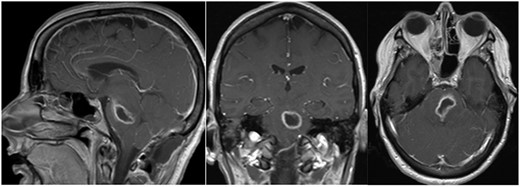

She presented to clinic for follow-up evaluation 11 weeks after discharge. Overall, she is doing very well and ambulating independently with a cane. On physical exam, CNII-XII are intact. She has no bulbar deficits. She has 4/5 strength in all major muscle groups on the right side. Repeat MRI has shown near resolution of the abscess (Fig. 3a and b).

Post-op axial and coronal MRIs, 11 weeks following discharge, demonstrating resolution of the pontine abscess with small area of residual scarring; source: http://pacsweb.wjmc.org.